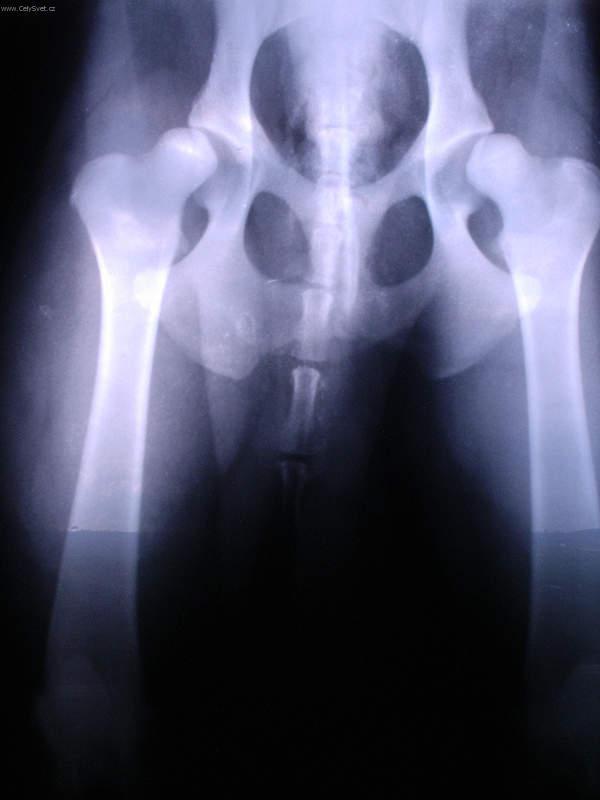

Fotogalerie > PSÍ SVĚT: Veterinární poradna > Ortopedie - DKK(www.celysvet.cz)Zobrazeno: 1209x (Datum vložení: 30.12.2005 000 18:51)www.CelySvet.cz > |